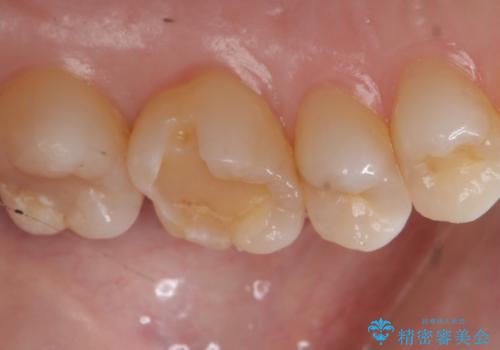

- 昔他院で虫歯治療をしたところが虫歯が再発したとのことで来院。

古い材料(プラスチックの樹脂)をとり、拡大鏡下で虫歯を全て取り除き、

ゴールドインレーにて治療しました。

歯の外側の面が少し欠けていて、そこの部分を覆う(ゴールドの範囲が広くなる)か

そこの欠けてる部分は虫歯ではないので削らないで、最小限にして詰め物を作るか相談したところ

欠けているところは何十年も昔から欠けていて特に何もない。なるべく歯を削りたくないとの事だったので

最小限で詰め物の治療をしました。